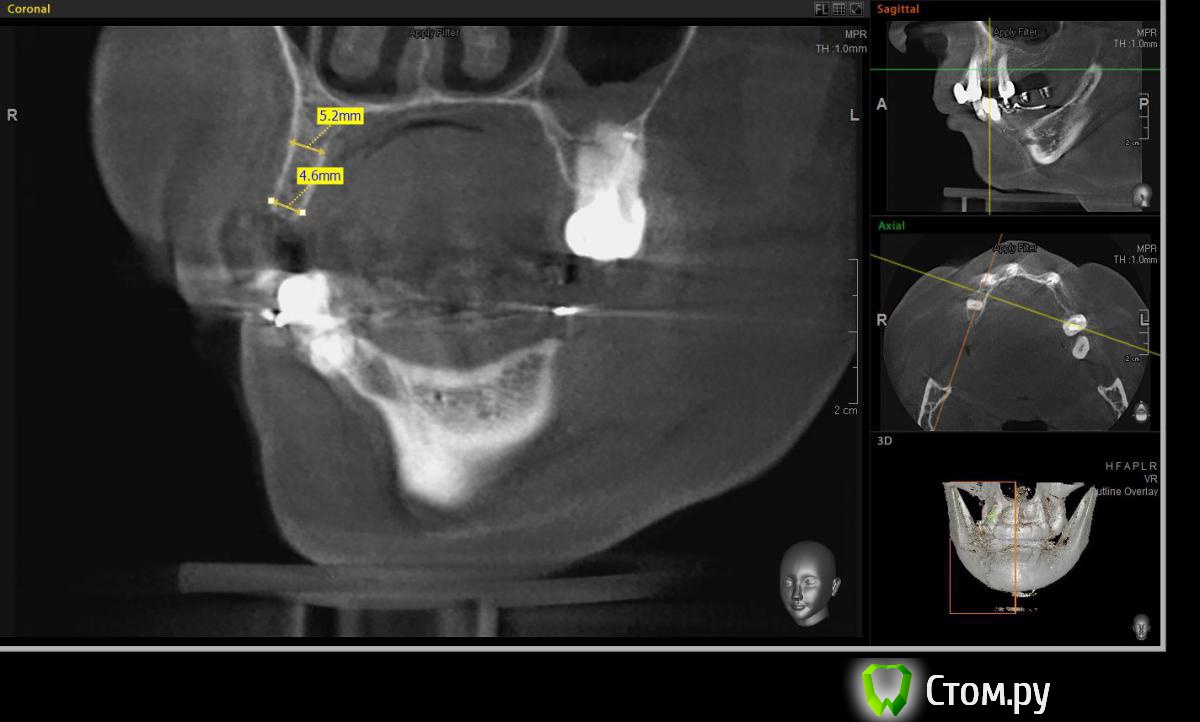

Евгений Ходыкин Опубликовано 23 июля, 2014 Поделиться Опубликовано 23 июля, 2014 Решили с пациенткой пока начать с в.ч. В планах имплантация в область отсутствующих 1.6, 1.4, 1.2, 2.1, 2.2, 2.4, 2.5. С 1.6 самому более менее все понятно, мануальных навыков хватит) Прошу помощи коллег относительно остальных областей. Фронт особливо печален... Забегая наперед скажу, что блоки еще не делал. Ауто точно пока брать не планирую, ибо нет даже теоретических навыков. Хочу начать все-таки с аллоблоков. У кого какие будут мнения, заранее спасибо) Ссылка на комментарий

Евгений Ходыкин Опубликовано 24 июля, 2014 Автор Поделиться Опубликовано 24 июля, 2014 В области 2.4 выраженная нёбная резорбция. Крепить мембрану туда, или все-равно наращивать вестибулярно?? Ссылка на комментарий